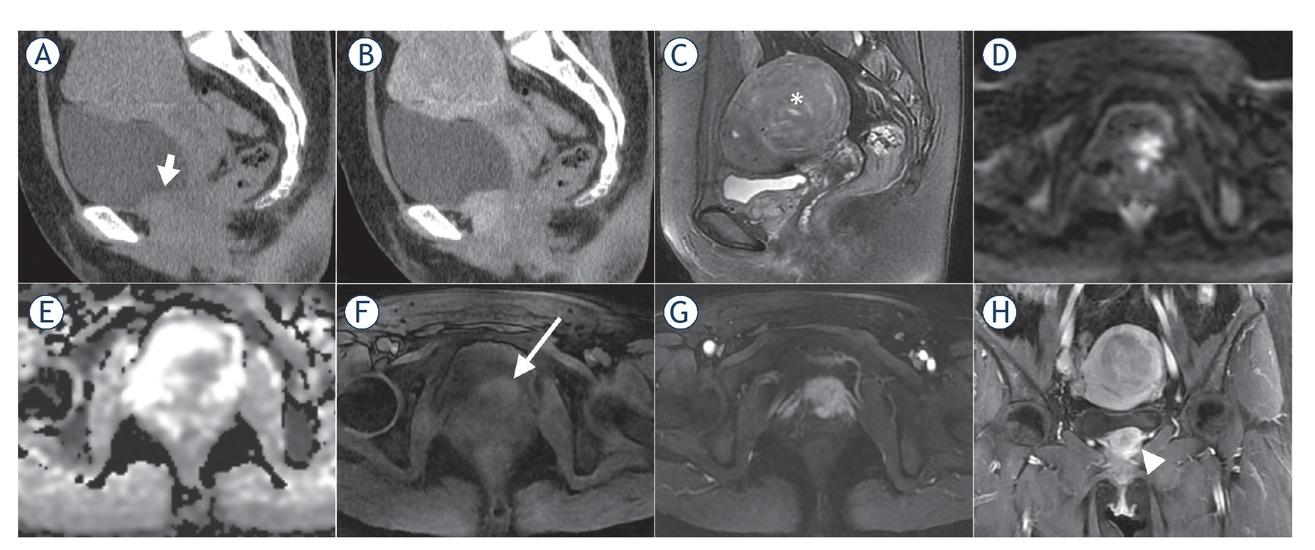

CT and MR images of a 47-year-old female with malignant bladder paraganglioma. The bladder tumour was located in the inferior bladder wall with an irregular shape and ill-defined margin, invading the adjacent tissues (short arrow). The tumour showed iso-density and moderate enhancement on sagittal pre- and post-contrast enhanced CT images (A, B), inhomogenous hyperintensity on sagittal T2-weighted images (T2WI) (C), hyperintensity on diffusion-weighted images (DWI) (D), hypointensity on apparent diffusion coefficient (ADC) maps (mean ADC value, 0.852 × 10-3 mm2/s) (E), inhomogenous slight hyperintensity compared to the gluteus maximus on T1-weighted images (T1WI) (long arrow) (F), heterogenous marked enhancement on arterial phase (G) and coronal contrast-enhanced images (arrowhead) (H). In addition, a uterine fibroid on the posterior wall of the uterus was also found (asterisk on sagittal T2WI).

On non-contrast CT images, the lesions mainly demonstrated homogeneous and soft-tissue density, with CT values ranging from 19.9 to 55.2 Hounsfield Units (HU). Intra-tumoural cystic degeneration or necrosis was rare (2/16). All lesions showed moderate to marked enhancement in the arterial phase of contrast-enhanced CT images (Table 3), with CT values of 64.3–117.9 HU, which were about 2.3 times that of the CT value on pre-contrast enhanced images (Figure 4A–B). In the two patients with multiple paragangliomas, the density and enhancement pattern of lesions in the non-bladder sites were similar to those in the bladder.

On T2WI, the lesions demonstrated homogenous hyperintensity (10/16), higher than the gluteus maximus and lower than the urine in the bladder, without typical “pepper and salt” sign. Due to the restricted diffusion, the lesions showed hyperintensity on DWI and hypointensity on ADC maps (mean ADC value ± standard deviation, 0.883 ± 0.126×10-3 mm2/s). On T1WI, the lesions showed hyperintensity and averaged 1.4 times higher than that of the gluteus maximus at the same layer. Following MRI enhancement, the BPGs all had obvious enhancement in the arterial phase (an average of 2.5 times higher than the tumour signal intensity on T1WI), slightly decreased enhancement in the venous phase and the delayed phase (an average of 2.4 and 2.0 times higher than the tumour signal intensity on T1WI, respectively), exhibiting a “fast in and slow out” enhanced pattern (Table 3, Figure 4C–D). Similar to CT findings, the two patients with multiple paragangliomas showed comparable MRI findings between the bladder and non-bladder lesions.

Imaging methods are primarily used for localization of the paraganglioma.11 In the absence of typical clinical manifestations and negative biochemical tests, imaging can also be used as a complementary approach for qualitative diagnosis. CT has a high sensitivity (82%) in detecting extraadrenal pheochromocytoma.9 We demonstrated that most BPGs are typically present as a solitary lesion protruding into or out of the bladder cavity, with an oval shape, soft tissue density, well-defined margin and a broad-base attachment to the bladder wall. The tumour exhibits slightly lower density and early marked enhancement on the contrast-enhanced CT images. Contrary to the previous literature, T2WI showed that BPGs are mostly homogeneous and high-intensity, without the typical “pepper and salt” appearance.12,13 The homogenous nature may be due to the fact that the lesion was still small when it was detected, and intratumoural degeneration has not yet occurred. Similar to bladder cancer, BPGs show marked hyperintensity on DWI and hypointensity on ADC maps due to restricted diffusion of water molecules.14 The tumours presented slight hyperintensity on T1WI and “fast in and slow out” enhanced pattern on contrast-enhanced images, which may be distinctive MRI features of BPGs.10,15 The potential pathological bases for the above imaging findings are that the tumour cells are large with abundant cytoplasm and the intercellular stromata are rich in blood vessels showing fissure or haemangiomalike dilatation.16

The malignant rate of BPGs is estimated to be 10–15%.9 Because no reliable pathological evidence exists for early differentiation between benign and malignant tumours, direct invasion of adjacent tissues or distant metastases are considered to represent potential malignancy.17 In this study, two lesions showed features of peripheral tissue invasion, suggesting malignancy. At present, dynamic contrast-enhanced MRI incorporating non-fat suppression T2WI with small FOV and high resolution, by means of the natural contrast between pelvic fat and urine in bladder, is the preferred imaging method for recognition of possible malignant tumours.18 In addition to CT and MRI, functional imaging is recommended to detect multi-focal and metastatic disease, such as 123I-metaiodobenzylguanidine (123I-MIBG) SPECT and 68Gallium-labeled somatostatin analogues (68Ga-DOTA-SSA) PET/CT. Depending on specific ligands that target specific cell membrane transporters or vesicular catecholamine transport systems, this modality can provide greater diagnostic specificity.12,19